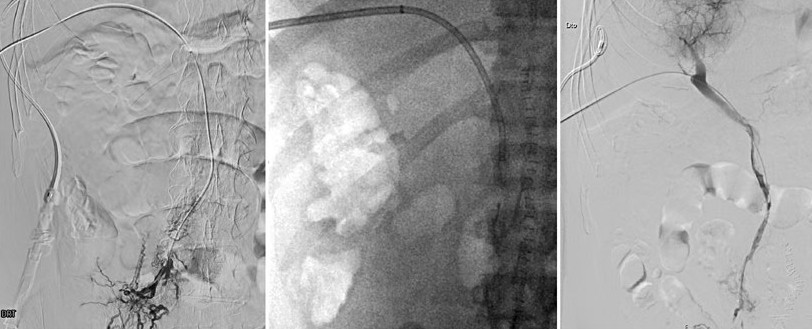

• Successful Endovascular Treatment of Acute Portal and Superior Mesenteric Vein Thrombosis in a Non-Cirrhotic Patient

Filipe Nery, Manuel Teixeira Gomes, Pedro Sousa

11-15

DOI: https://doi.org/10.60591/crspmi.555